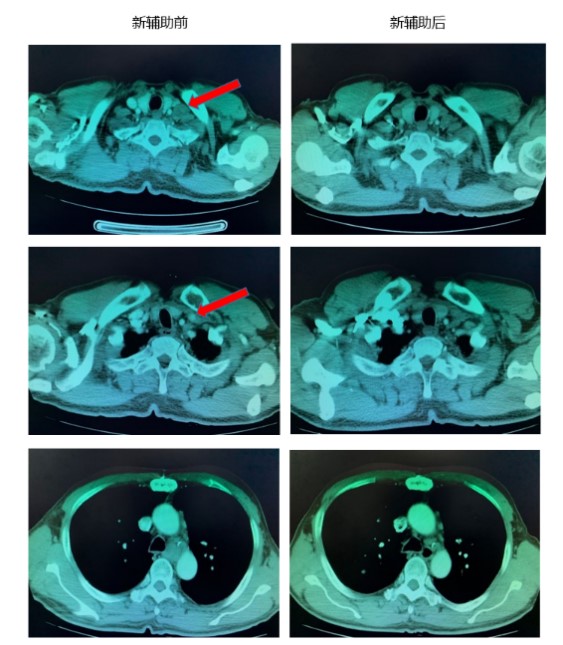

考虑到新辅助治疗有效,在进行术前评估后,于2019年08月20日行胸腹腔镜联合食管癌切除+胃代食管左颈吻合+颈胸腹三野淋巴结清扫+空肠造瘘术+右上肺楔形切除术。如图。

术后病理结果:(食管)原瘤床经全部取材镜下见小灶鳞状上皮呈高级别上皮内瘤变,间质纤维组织增生伴慢性细胞浸润。病理结果显示到达MPR, “食管切端”胃切端未见肿瘤。各组淋巴结未见转移癌(注:左锁骨上淋巴结病理转阴)。(右上肺结节)镜下见坏死结节。

结果显示,术前新辅助治疗取得很好的疗效,影像学检查提示病灶明显缩小,评价PR。术后病理提示肿瘤退缩明显,对治疗反应良好。